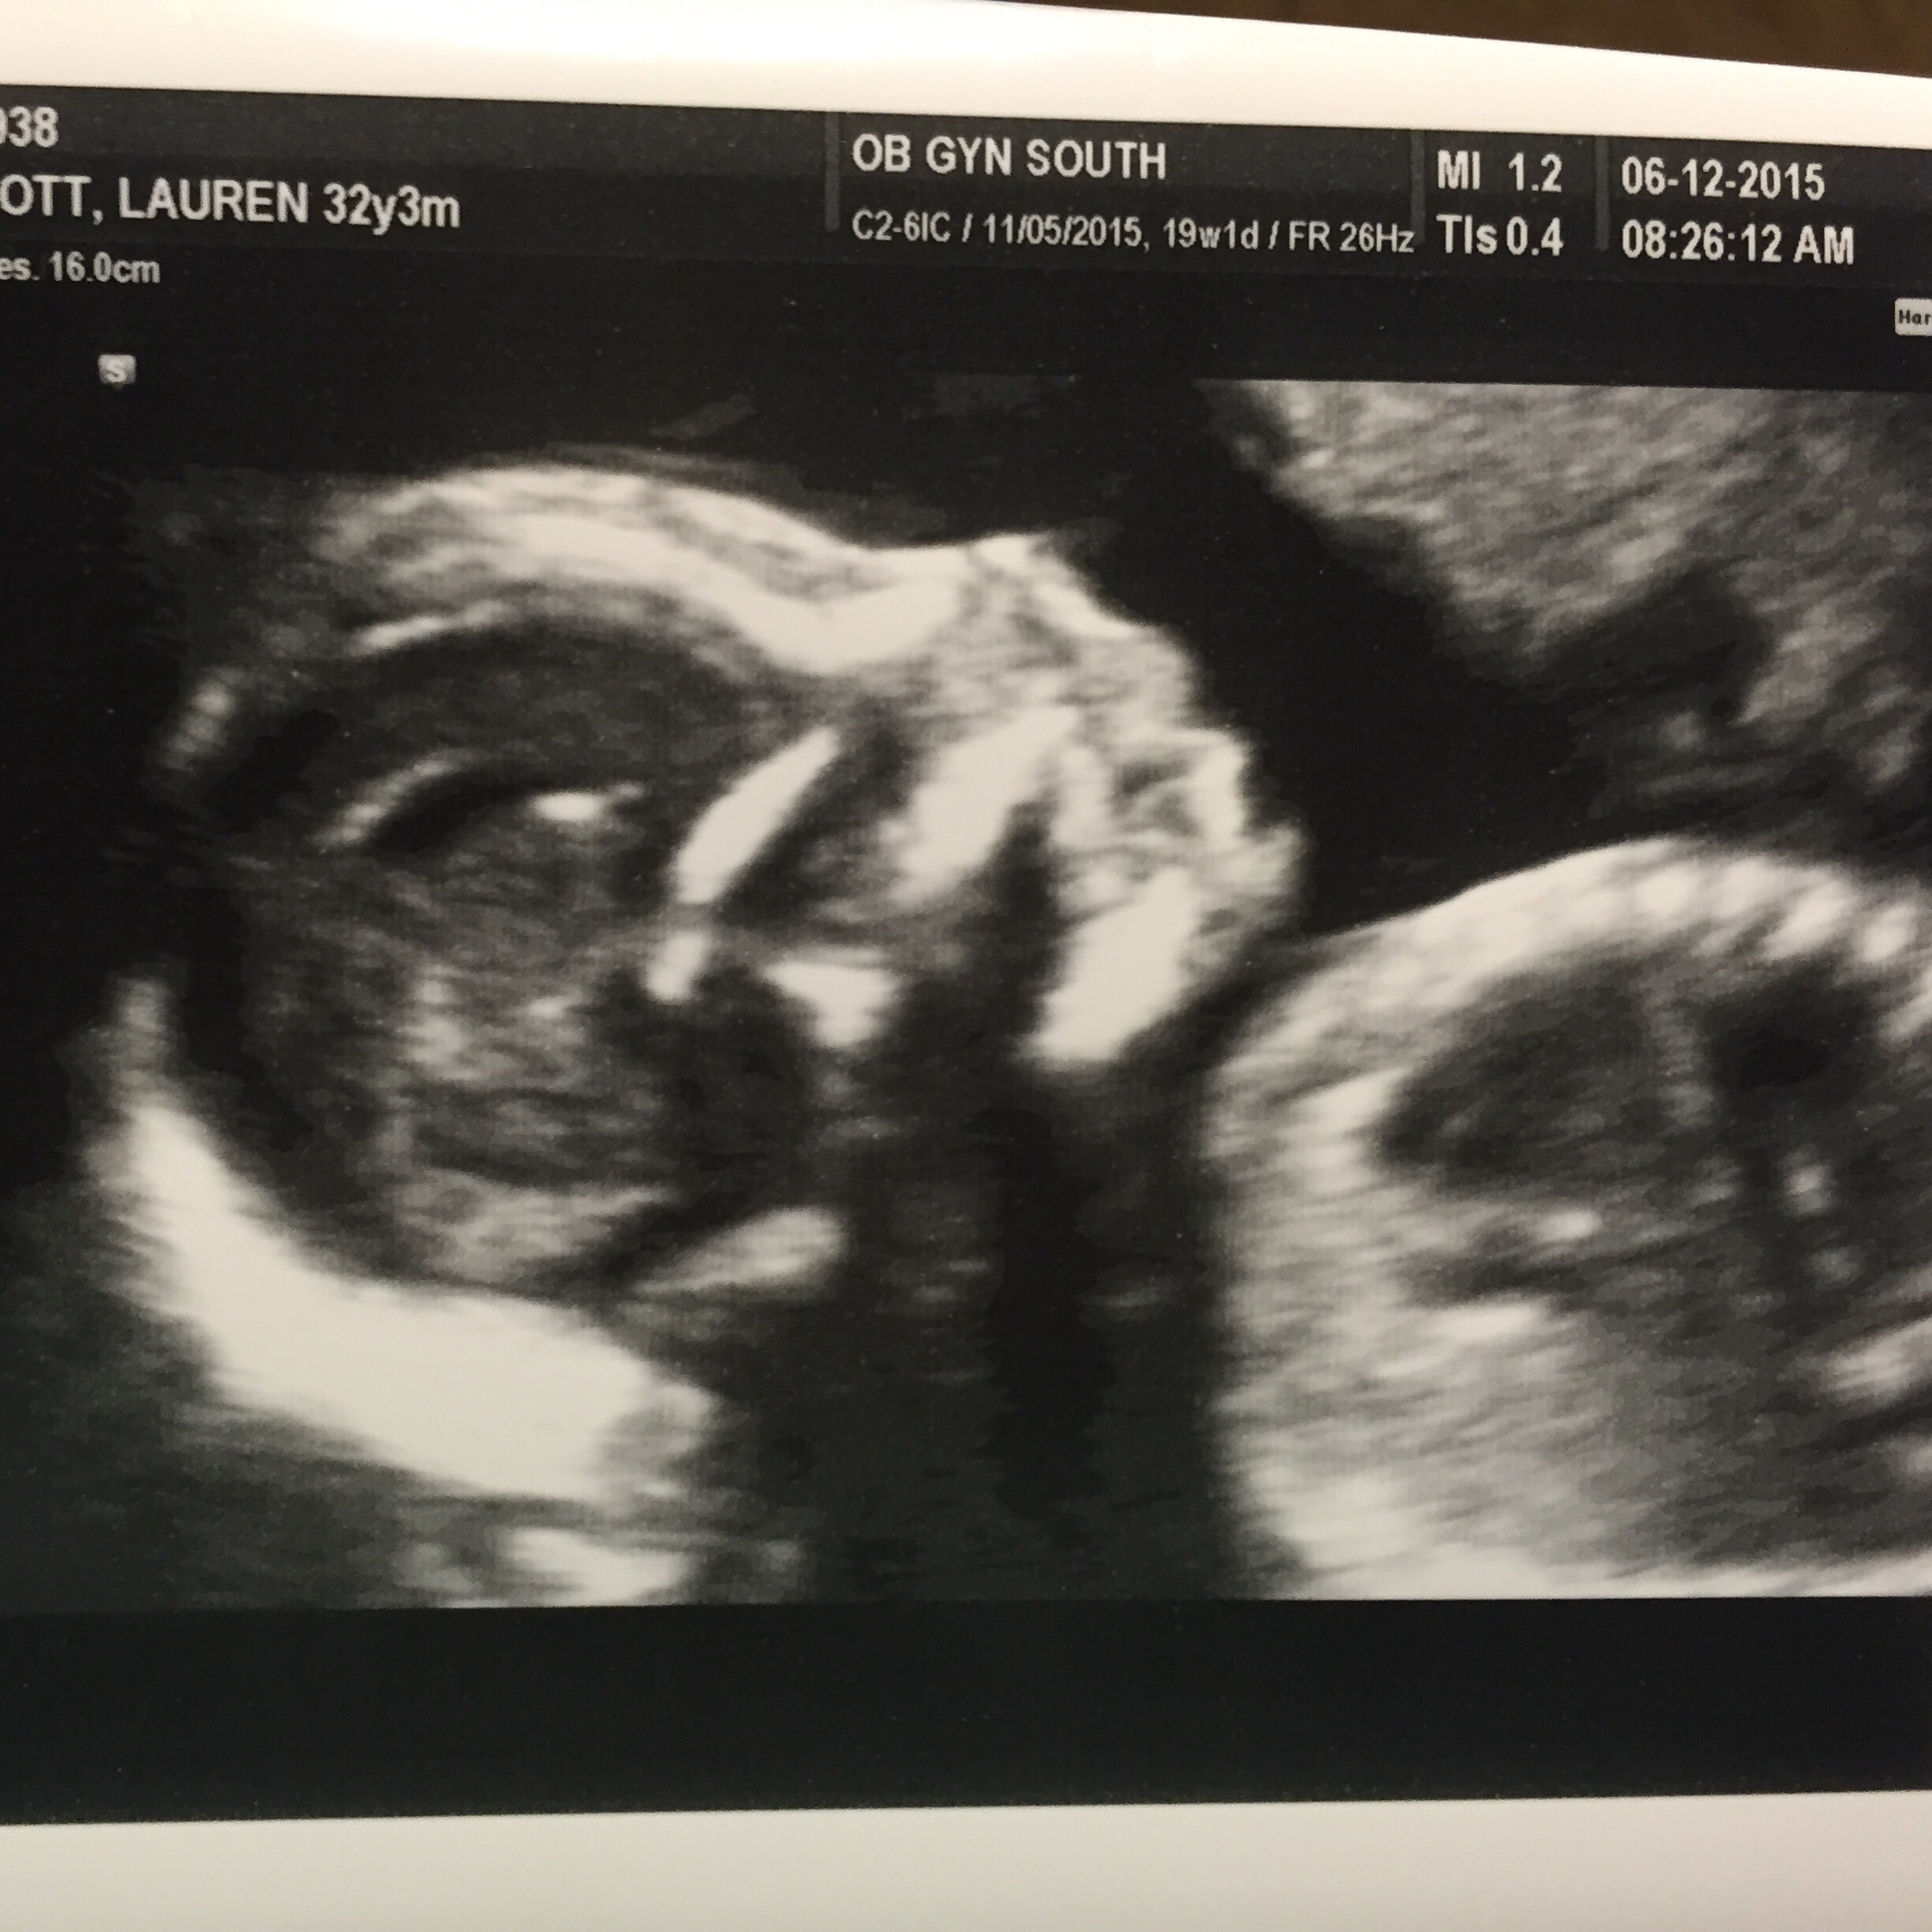

This was last Saturday at 12w3d. My best friend is a sonographer so she got me in. She wanted to try and guess if baby is a boy or girl. When we go by the nub theory it's a boy! She said she's pretty confident. When she was pregnant She knew she was having a girl this early so we will see if she's right!!